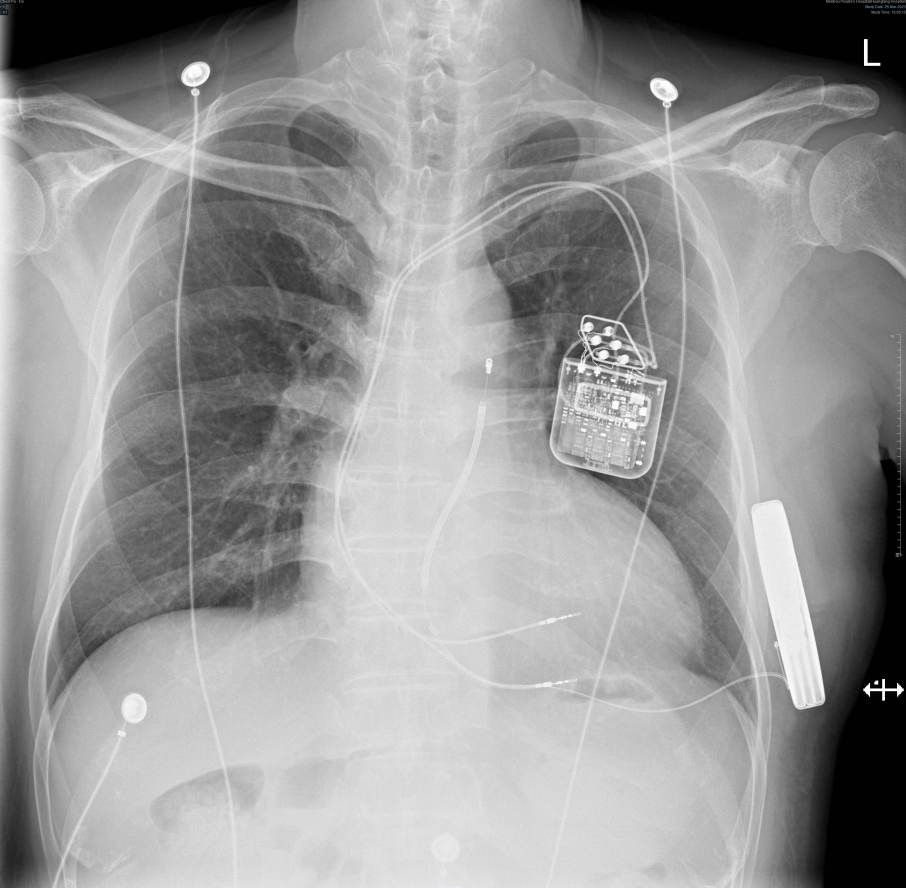

CCM与S-ICD植入术后影像